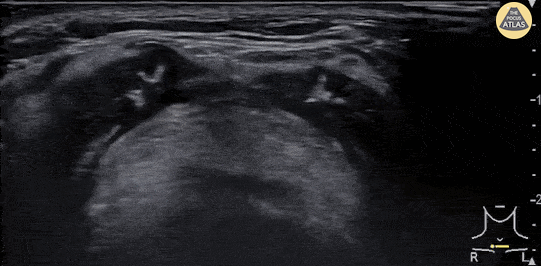

Soft Tissue - Epiglottitis

A 30 year-old female presented to the emergency department with high fever, severe sore throat and shortness of breath. POCUS of the neck was performed and revealed a swollen epiglottis, especially in the right side. Further X-ray of the neck revealed thumb sign and nasopharyngoscopy showed epiglottitis with swelling of right tongue base and arytenoid. Although the normal range of the epiglottis thickness measured by ultrasound varied from 2 to 3 mm in previous studies, significant swelling and thickening of the epiglottis on ultrasound may indicate epiglottitis. Chi-Hsin Chen